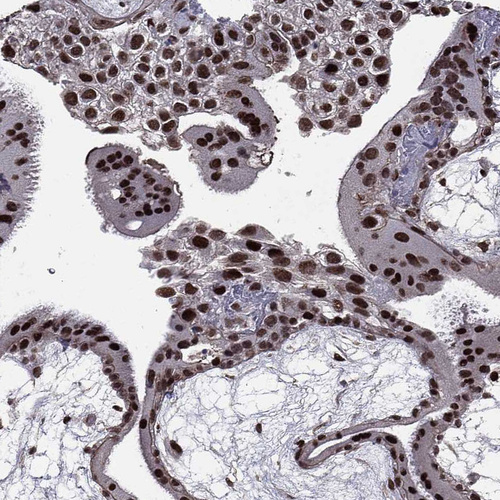

Immunohistochemistry analysis in human placenta and pancreas tissues using HPA004174 antibody. Corresponding RARB RNA-seq data are presented for the same tissues.